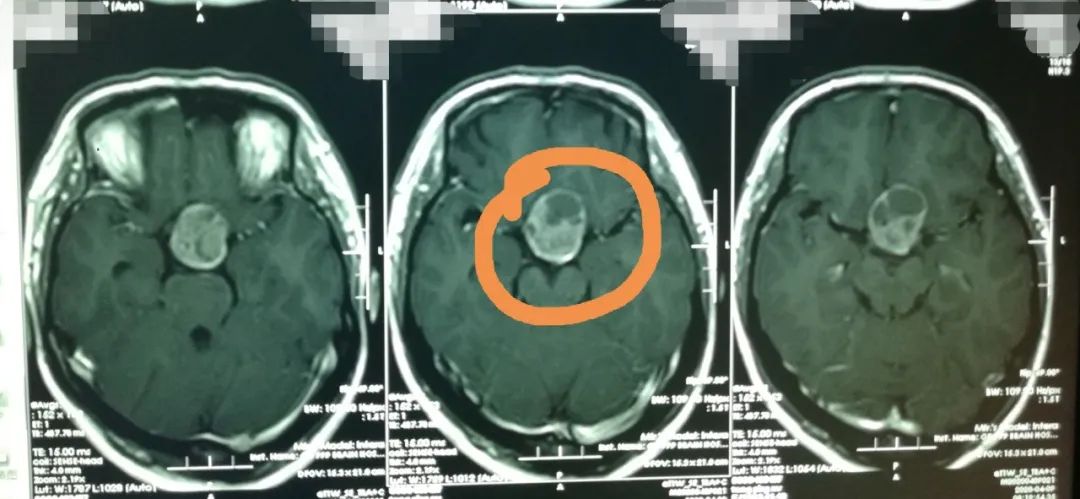

入院完善头颅CT检查后,鲁明发现她鞍区有巨大占位性病变。“根据影像检查结果,并且考虑到患者一直怀不上二胎、内分泌紊乱,所以初步认为是垂体瘤的可能性较大。”

肿瘤压迫并损害了视觉神经纤维,导致该患者出现头痛、双眼外侧偏盲和视力下降等症状。鲁明分析,如果继续放任不管,肿瘤会继续压迫大脑神经,进一步影响患者视力,甚至很可能会失明。

完善相关检查后,鲁明为患者实施了鞍区占位性病变切除术,成功切除了一个直径大小约5.0cm的瘤子。术后病理诊断为促肾上腺皮质激素细胞腺瘤。